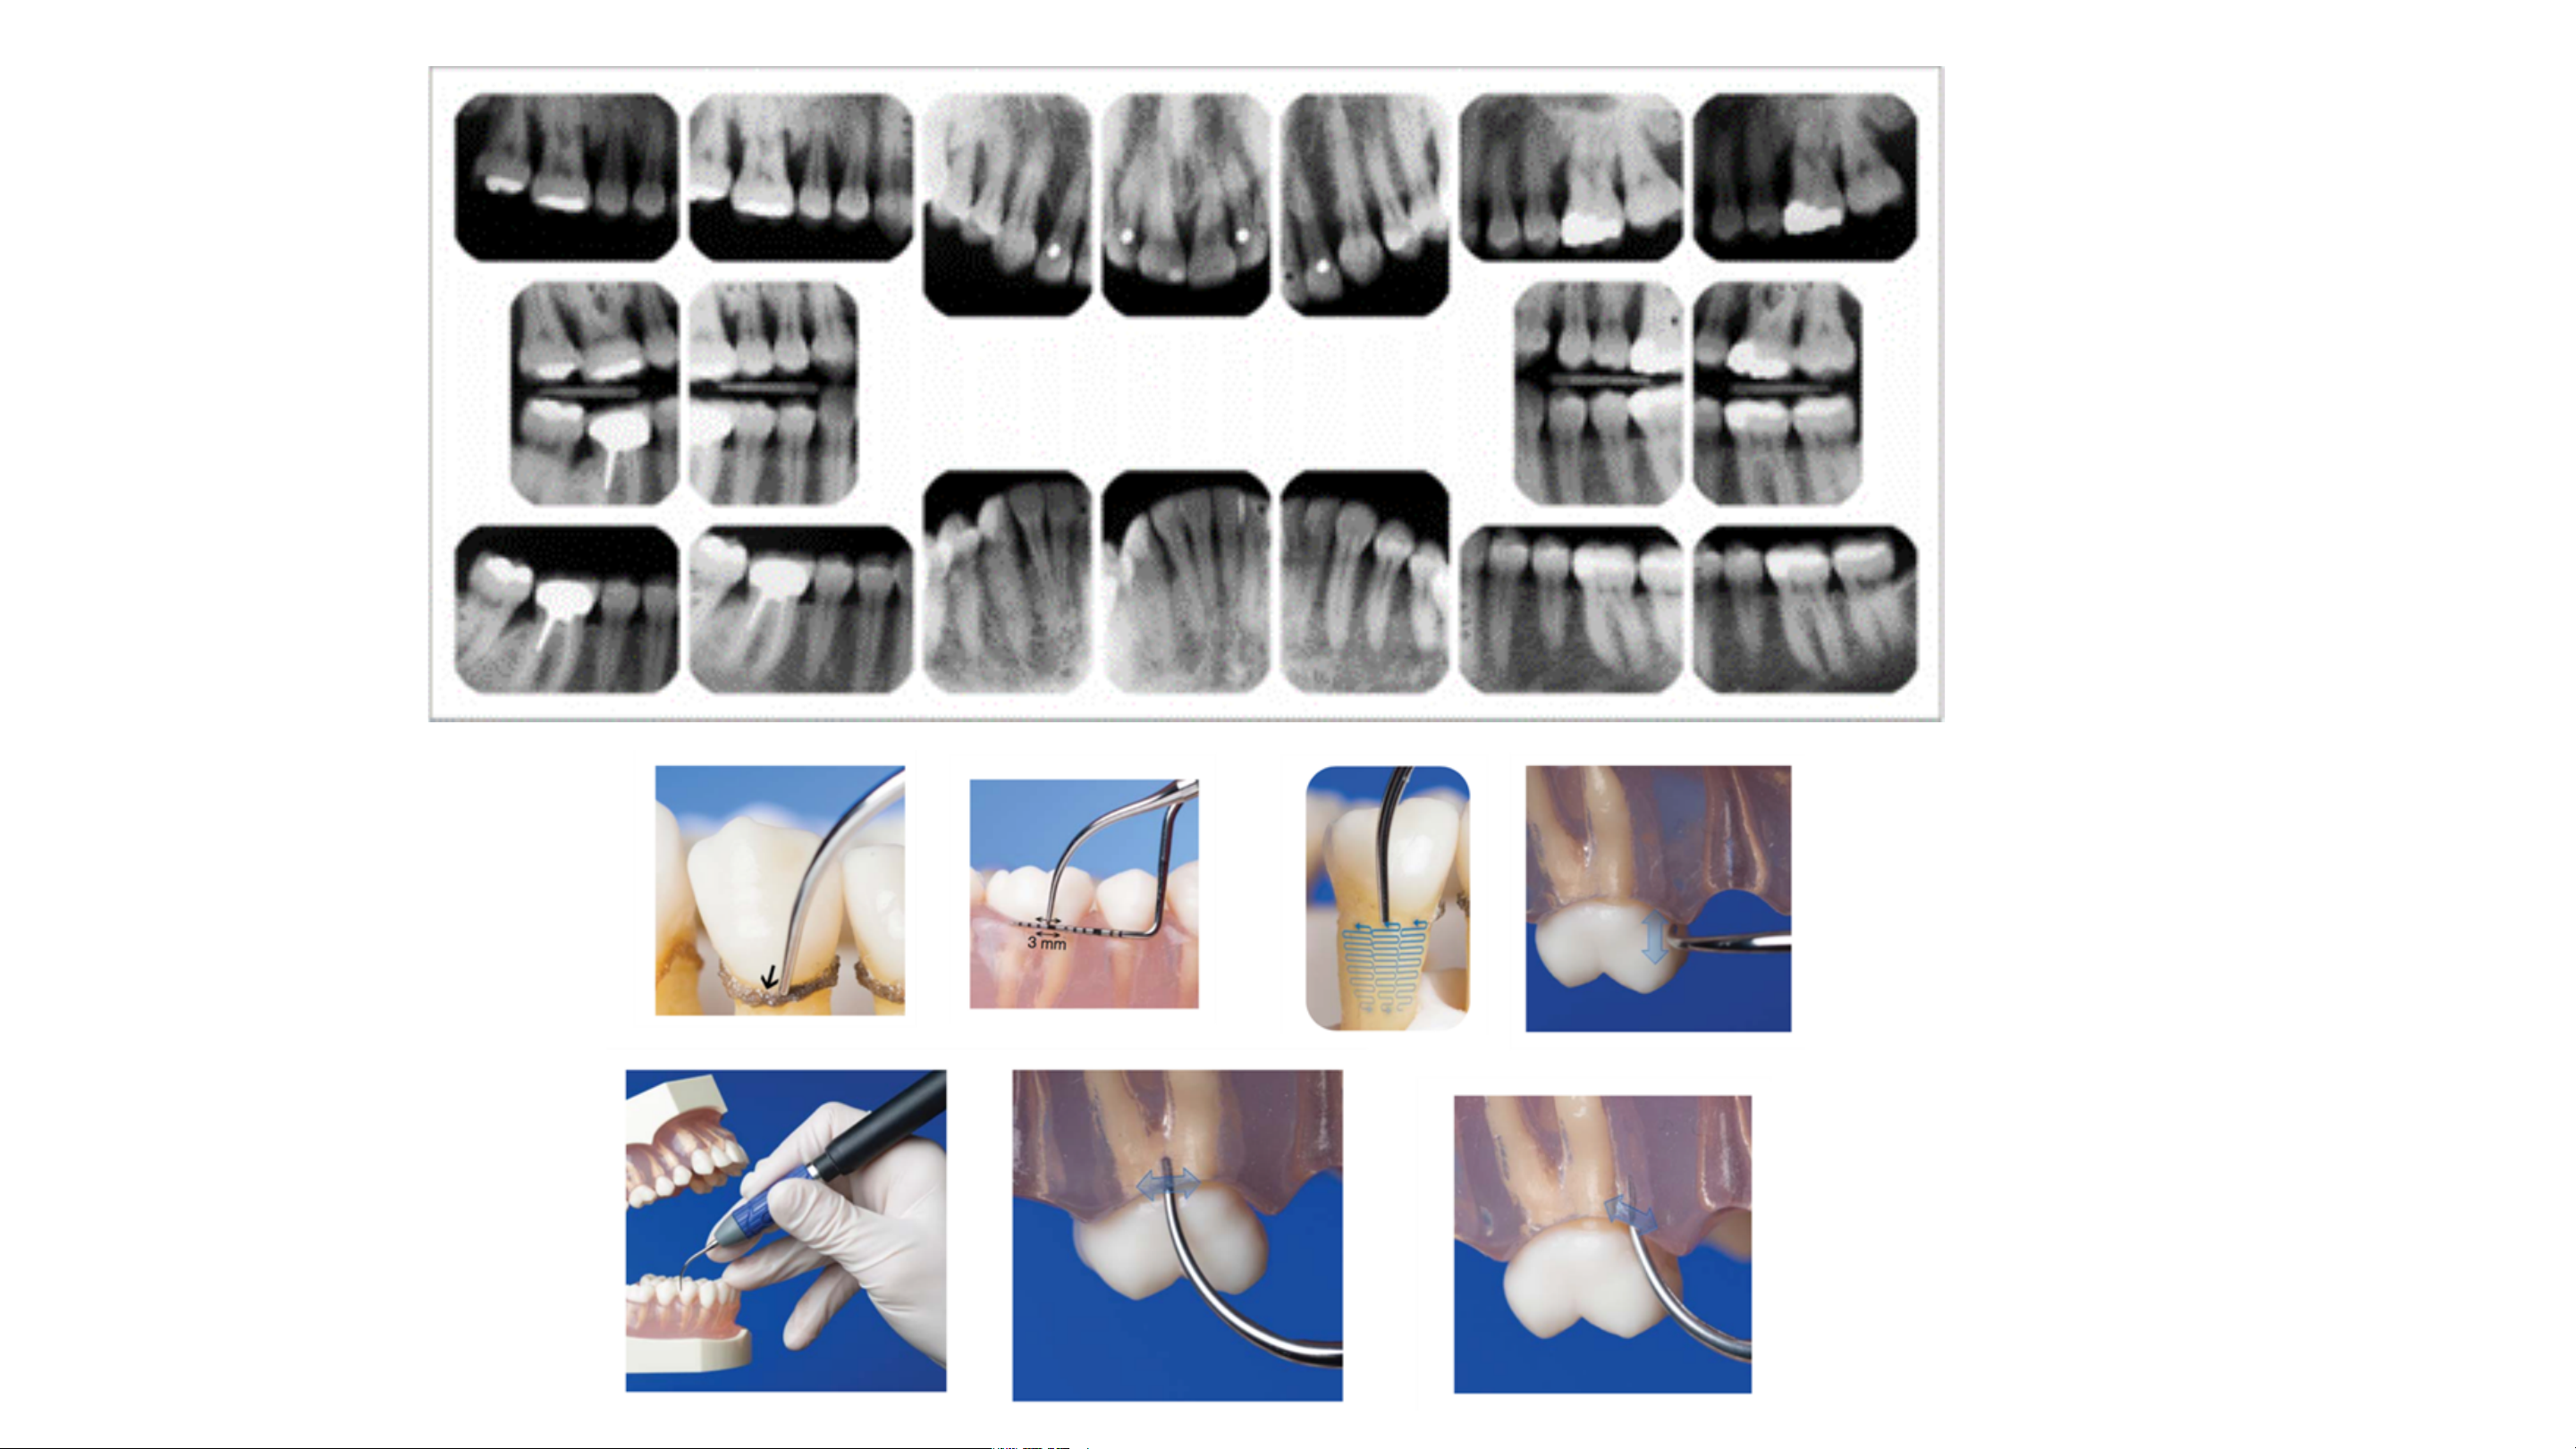

DỤNG CỤ CÂY ĐO TÚI NƯỚU

Nguồn: Newman, M.G.,Takei,H.H.,Klokkevold, P.R., et al. (2019).

Newman and Carranza’s Clinical Periodontology (13th ed.). Philadelphia: Elsevier. HÌNH ẢNH VÀ TLTK: BM NHA CHU KHOA RHM, HIU. TP HCM